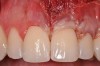

Various procedures to correct deficient gingival contours have been well documented in the dental literature.1,2 Increasing zones of attached gingiva using palatal donor tissue and the free gingival grafting procedure was introduced by Björn almost a half century ago.3 Using palatal donor tissue in the form of a free soft-tissue autograft for root-coverage procedures was reported by Miller.4 Additional procedures were reported using lateral5 or coronal repositioning6-8 of the adjacent attached gingiva via a pedicle flap or the coronal repositioning of previously grafted tissue.9,10 Miller also reported on gingival grafts placed over root surfaces to correct areas of deep-wide gingival recession.11 Further surgical advancements led to the use of subepithelial connective tissue from the palate to obtain root coverage.12-14 Figure 1 shows the pretreatment view of a mandibular central incisor, and Figure 2 depicts the post-treatment view of the site treated with a subepithelial connective tissue graft harvested from the patient’s palatal tissues.

Fig 1. Preoperative clinical view, mandibular central incisor.

Figure 1

Fig 2. Post-treatment clinical view after subepithelial connective tissue graft.

Figure 2